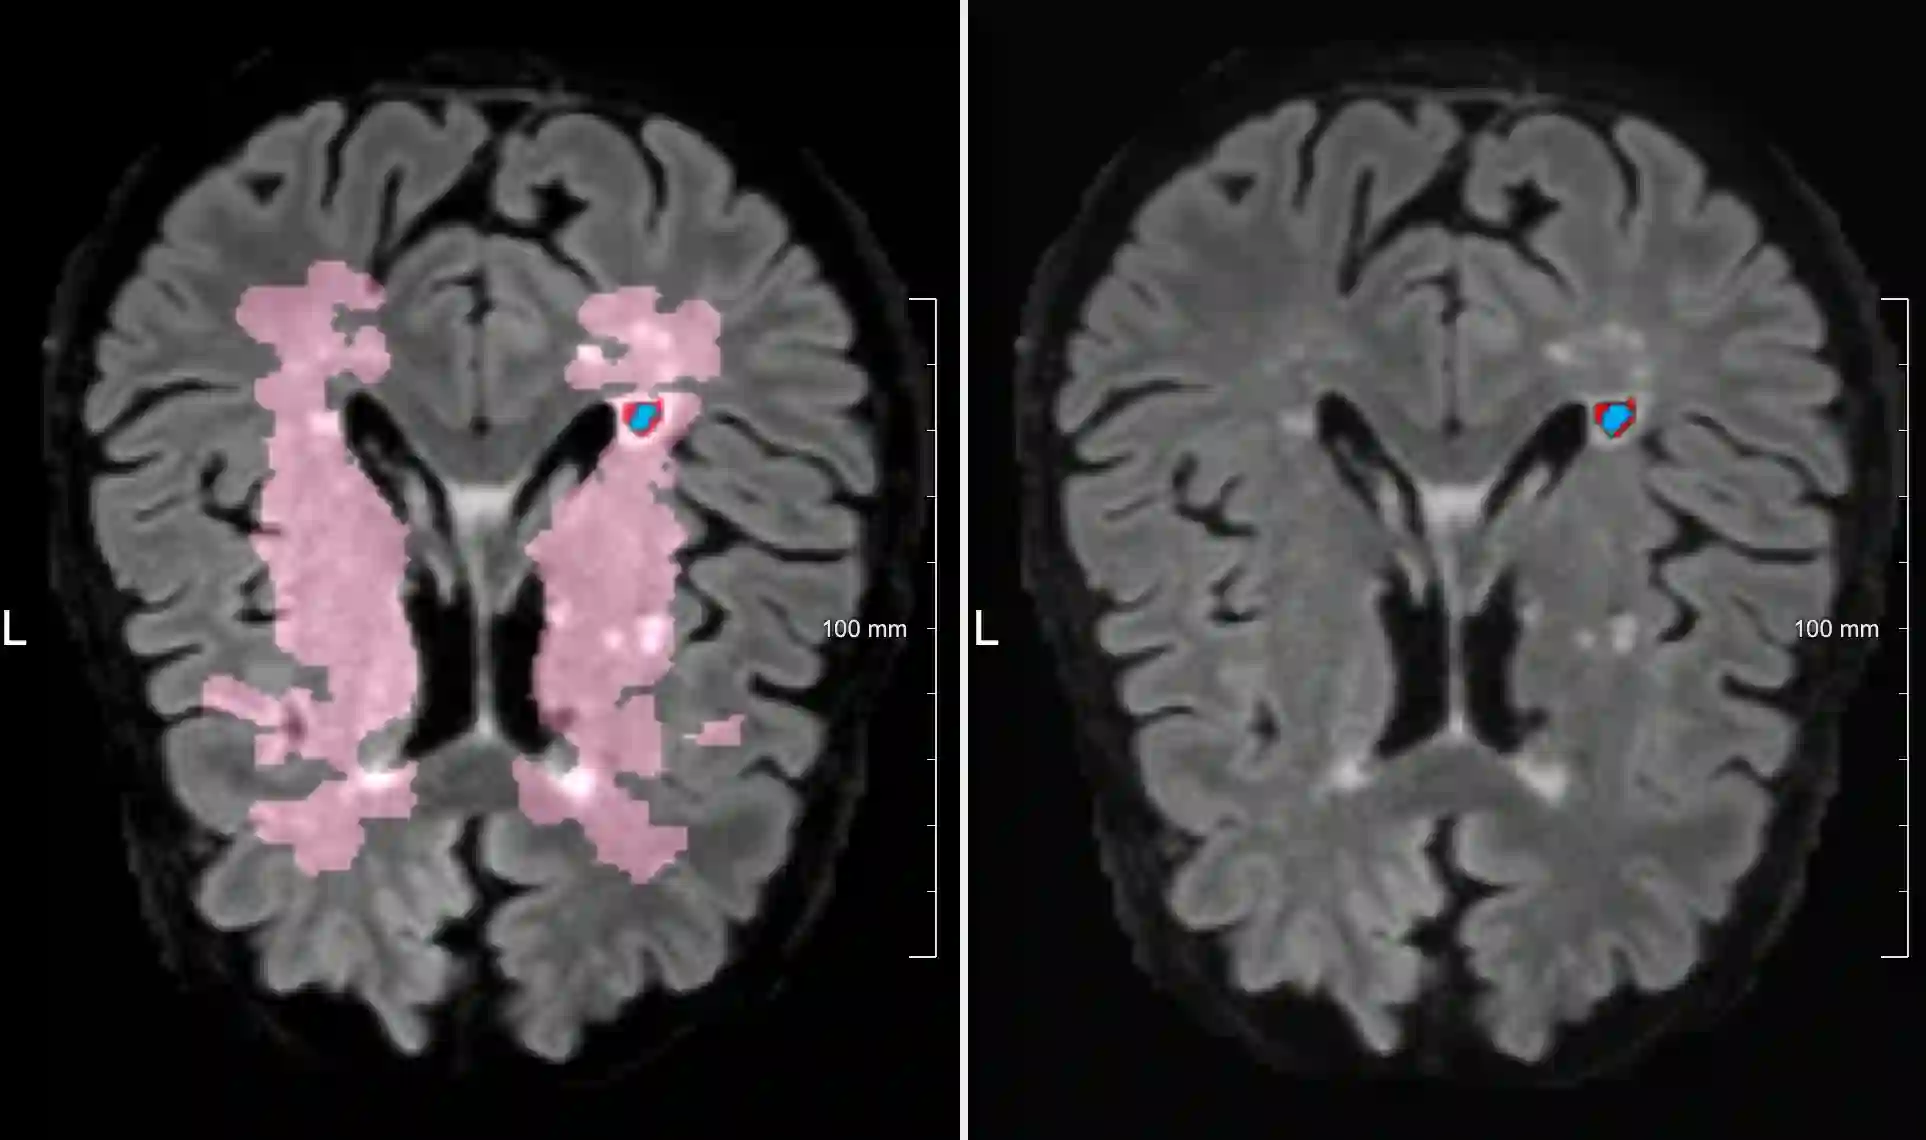

Lacunes of presumed vascular origin are fluid-filled cavities of between 3 - 15 mm in diameter, visible on T1 and FLAIR brain MRI. Quantification of lacunes relies on manual annotation or semi-automatic / interactive approaches; and almost no automatic methods exist for this task. In this work, we present a two-stage approach to segment lacunes of presumed vascular origin: (1) detection with Mask R-CNN followed by (2) segmentation with a U-Net CNN. Data originates from Task 3 of the "Where is VALDO?" challenge and consists of 40 training subjects. We report the mean DICE on the training set of 0.83 and on the validation set of 0.84. Source code is available at: https://github.com/hjkuijf/MixLacune . The docker container hjkuijf/mixlacune can be pulled from https://hub.docker.com/r/hjkuijf/mixlacune .